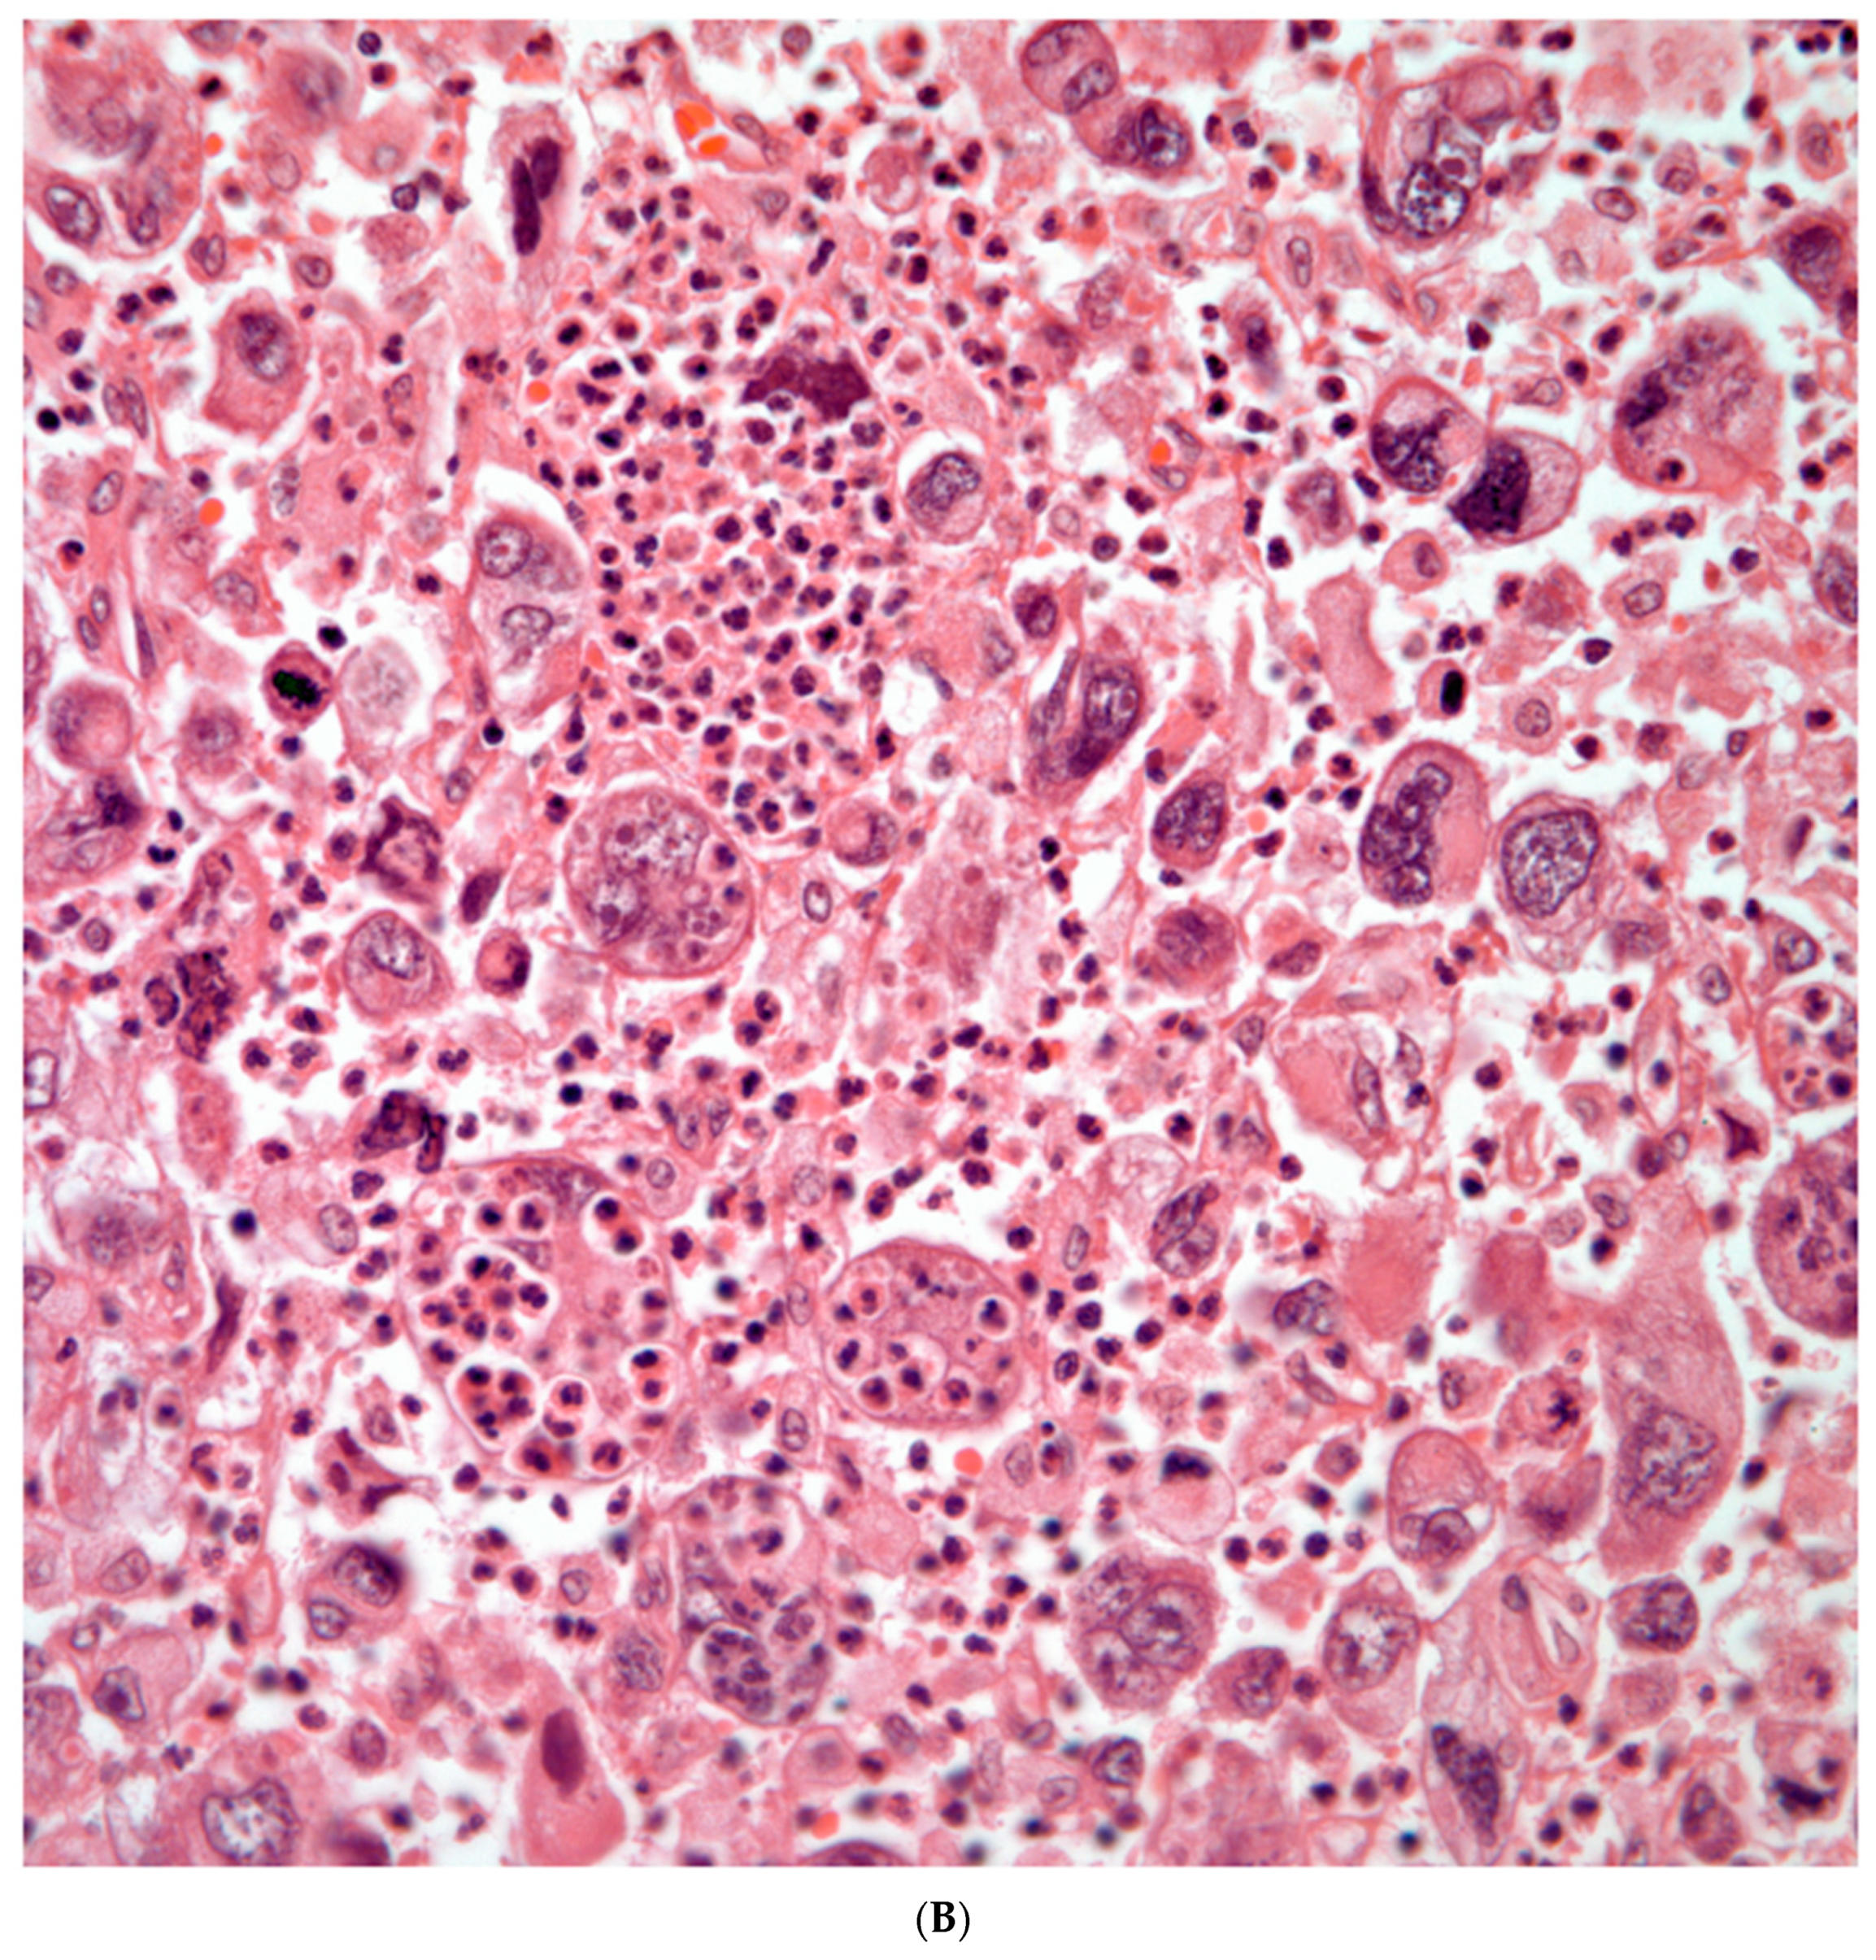

Giant Cell Carcinomas: these tumors may show predominantly a neoplastic cellular proliferation composed exclusively of multinucleated giant cells or a predominantly giant cell carcinoma (Figure 5A,B) or associated with a conventional non-small cell carcinoma such adenocarcinoma or squamous cell carcinoma. The giant cell carcinoma may show giant cells of the syncytiotrophoblastic, osteoclastic, or null cell type. The giant cell carcinomas of the null cell type characteristically show a prominent inflammatory background and giant cells engulfing inflammatory cells (emperipolesis) (Figure 6A,B). The tumors composed of osteoclast-like giant cells show giant cells like those described in bone tumors (Figure 7A,B)

Figure 5. A) Predominantly giant cell carcinoma; B) Marked atypia and numerous multinucleated malignant giant cells.